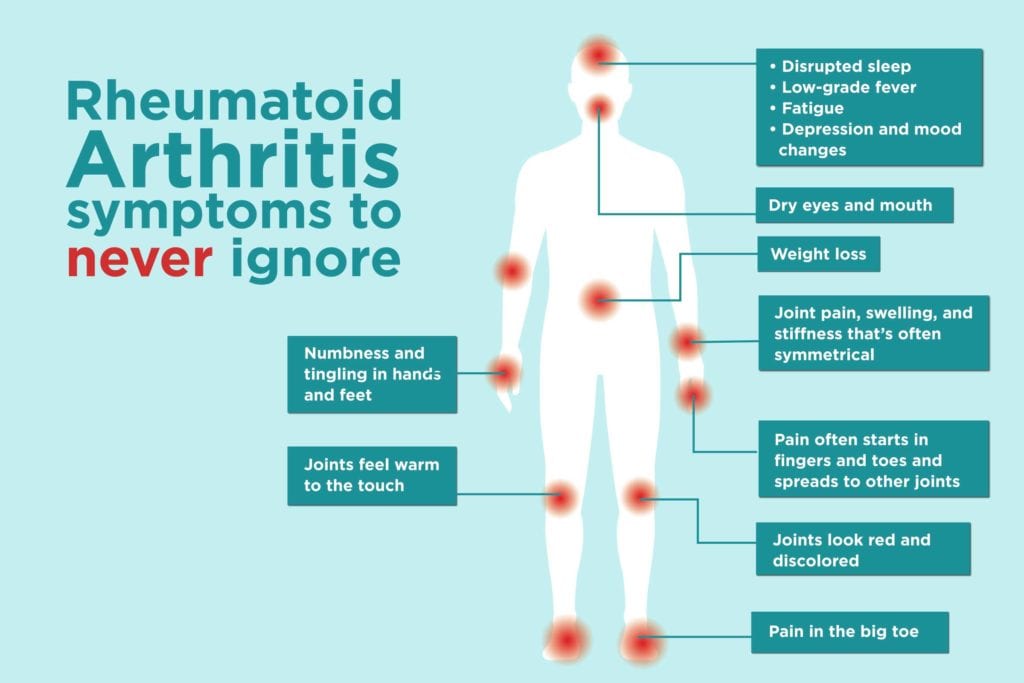

Rheumatoid Arthritis Symptoms You Might Be Ignoring